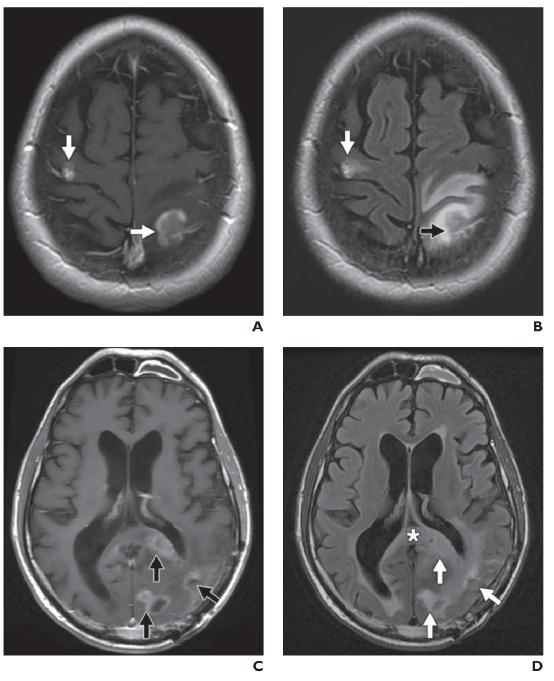

图7——肿瘤血管源性水肿。A,在伴有颅内黑色素瘤转移的1型水肿患者中,增强T1-加权图像显示右侧额叶和左侧顶叶的增强肿块(箭头)。B,FLAIR序列显示与A相同的病灶周围水肿,界限清楚,局限于肿块附近(箭头)。C,在多灶性多形性胶质母细胞瘤2型水肿患者中,对比增强T1加权成像显示左侧枕叶有多个强化病灶(箭头)。D,FLAIR序列显示弥漫性浸润性水肿(箭头),反映肿瘤微浸润。穿过胼胝体压部中线(星号)。

上图已经描述了两种不同类型的瘤周血管源性水肿。1 型可见于低级别和非神经胶质肿瘤的紧邻区域,例如脑膜瘤和转移瘤。这种类型被认为继发于脑实质压迫,继发性缺血和坏死甚至在肿瘤切除后仍然存在(图 7A )。2 型水肿发生在高度浸润性高级别神经胶质瘤中,会引起血脑屏障的额外紊乱。这种水肿模式遍及同侧大脑半球,指状突起反映肿瘤微浸润(图 7B )。切除后,数月内水肿可能会部分或完全消退。与 1 型水肿相比,2 型水肿 DWI 的扩散系数增加,DTI 的各向异性分数降低,这可能反映了恶性细胞浸润造成的实质破坏更大。当见于小肿瘤或良性肿瘤时,这种非典型水肿模式高度怀疑恶性变性。